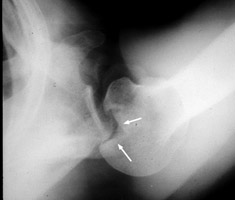

Posterior shoulder dislocation

Trough line is seen with posterior shoulder dislocation. When the humeral head is forced posteriorly in internal rotation, the anterior aspect of the humeral head is driven against the posterior glenoid rim. With sufficient force, the head will sustain a compression fracture. In many cases of posterior dislocation of the shoulder, two parallel lines of cortical bone can be seen. The outer (more medial) cortical line represent the medial cortex of the humeral head, while the other line represents the margin of a "trough" like impaction fracture.